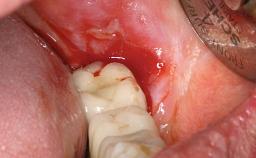

In 2004, the patient, a smoker, began dental treatment at the ACTA graduate clinic. She was a TV producer exposed to a lot of stress in her job and had a sick husband. Her maxillary teeth had been extracted, as had the mandibular canines, premolars, and molars, with the exception of tooth 34. She received a complete maxillary denture and a mandibular skeleton denture. In October 2007, her maxilla was augmented by an oral and maxillofacial surgeon; in March 2008, implants (Biomet 3i, Palm Beach, Florida, USA) were inserted at that same clinic. In 2008, the patient was presented at the Department of Oral Implantology and Prosthetic Dentistry to request restorations for her implants. An implant-supported overdenture was planned. She also asked if we could restore her occlusion with fixed prosthetics.